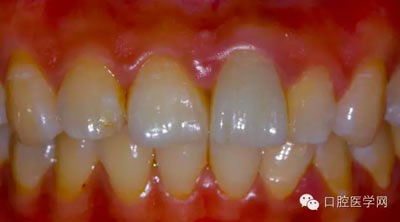

8、術(shù)前術(shù)后對(duì)比

6、術(shù)后一周照,牙齦恢復(fù)良好

5、3MU200樹(shù)脂粘接劑粘固全瓷冠術(shù)后照